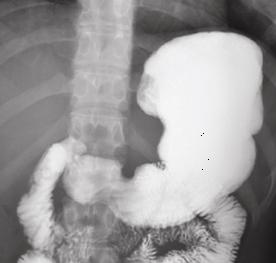

Images normales de estomac , bulbe et

duodenum expose en serie |

TOGD de estomac en position debout de

face . Image en chaussure de l.estomac . |

Estomac en debout

, profile droit expose |

Estomac en decubitus ventral OAD |

|

Decubitus OAD .

Antre et portion verticale est en pliine de baryte

. Arcade duodenum est bien detecte et en vue

nettement |